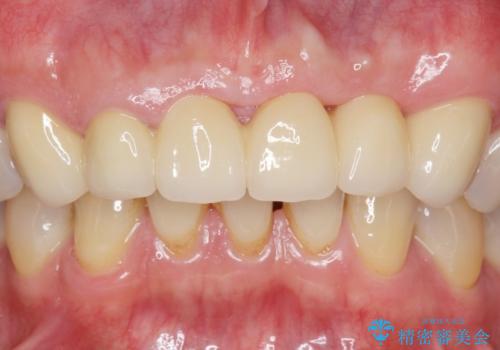

転んで前歯が2本ぬけた 自然なブリッジへ 60代男性

自然な仕上がりと咬み心地に大変ご満足頂けました。

「以前は出っ歯だったのにブリッジにしたことで歯並びもきれいになった!」と喜んで下さいました。

クラウンの種類:オールセラミッククラウン スタンダード